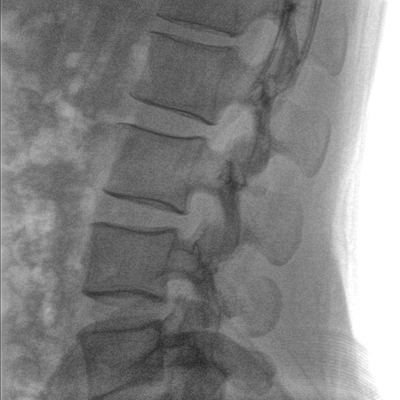

大尺寸液晶顯示器,圖像顯示清晰細膩;顯示器可大角度旋轉,滿足臨床多角度觀察圖像的需要。